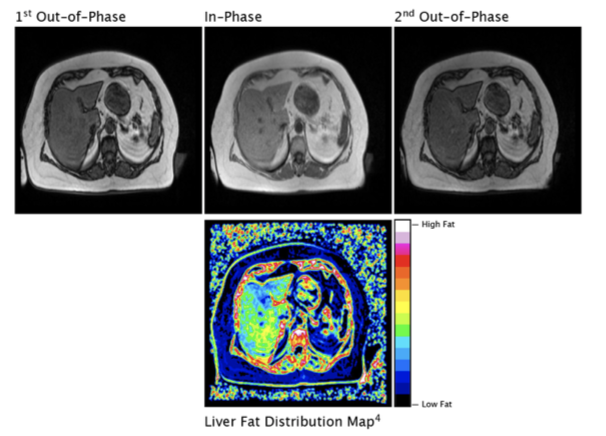

| FerriSmart: A FDA, TGA and CE Mark cleared AI solution to automatically detect Liver Iron Concentration from MRI scans: https://ferriscan.com/ferrismart/ HepaFat-AI: An FDA cleared AI solution to automatically detect Liver Fat Concentration from MRI scans: https://www.hepafat.com ALERT-PE: Currently in the R&D phase, ALERT-PE is an AI based tool for the detection of suspected Pulmonary Embolism (PE) from CT scans: https://www.resonancehealth.com/news/latest-news/218-r-d-update-new-pulmonary-embolism-ai-solution-developed.html |